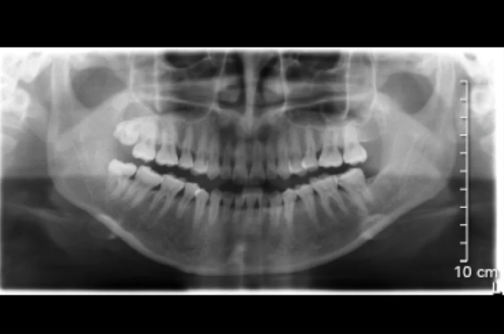

齦下刮治是通過專業(yè)的器械對于齦下的牙周組織進(jìn)行深度清潔,包括根面清洗和病理性軟組織的處理。這可以去除齦下的菌斑和牙石,減少牙齒周圍的炎癥,促進(jìn)口腔組織愈合,從而達(dá)到預(yù)防和治療牙周炎的目的。